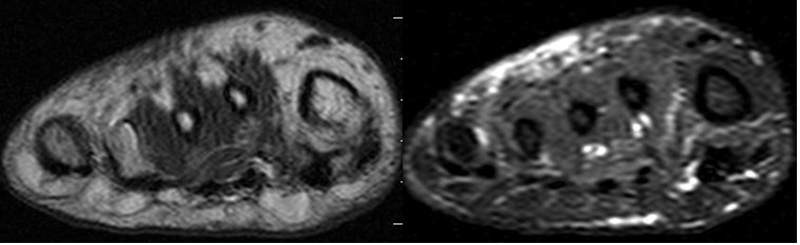

Fig 125 B. Edema en pie diabético.

A: RM axial simple en T1 y B: RM axial en T1 con contraste. Cambios inflamatorios en el tejido celular subcutáneo del pie, hipointenso en T1. No hay realce con el contraste, por inflamación sin infección.